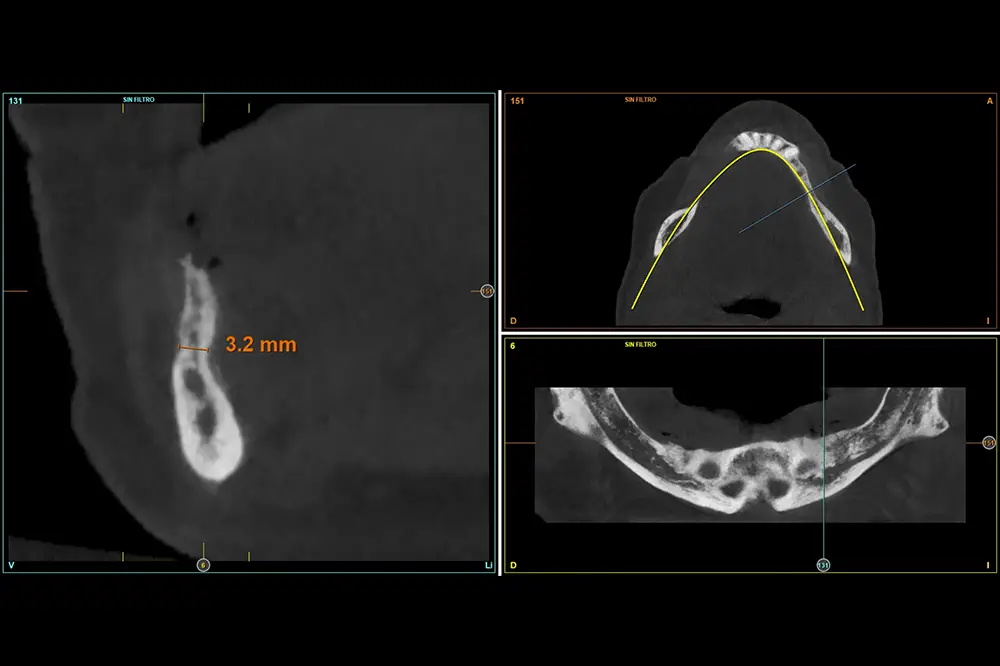

Figuras 12-15. En el cuarto cuadrante, la situación es muy similar, planificándose de nuevo implantes de 2,5 mm.